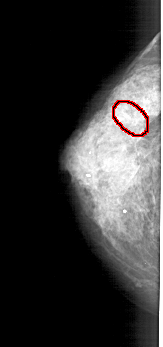

A_1430_1.LEFT_MLO

FILE: A_1430_1.LEFT_MLO.OVERLAY

TOTAL_ABNORMALITIES 1

ABNORMALITY 1

LESION_TYPE CALCIFICATION TYPE AMORPHOUS DISTRIBUTION CLUSTERED

ASSESSMENT 4

SUBTLETY 1

PATHOLOGY BENIGN

TOTAL_OUTLINES 1